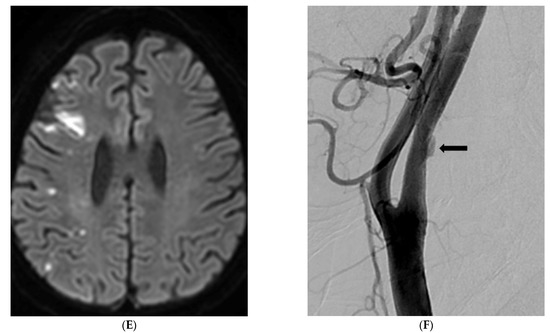

Background: To determine the prevalence of symptomatic nonstenotic carotid disease (SyNC) using simultaneous non-contrast angiography and intraplaque hemorrhage (SNAP) imaging for patients with acute stroke as an MR screen protocol and to assess imaging findings of carotid plaques. Patients and Methods: From May [...] Read more.

Background: To determine the prevalence of symptomatic nonstenotic carotid disease (SyNC) using simultaneous non-contrast angiography and intraplaque hemorrhage (SNAP) imaging for patients with acute stroke as an MR screen protocol and to assess imaging findings of carotid plaques. Patients and Methods: From May 2020 to October 2021, 2459 patients with suspected acute neurological symptoms were evaluated with brain diffusion-weighted imaging (DWI) and carotid SNAP imaging. We analyzed the degree of stenosis and intraplaque hemorrhage (IPH) using SNAP imaging. Prevalence of SyNC and risk factors for stroke in patients with SyNC were determined. We performed subgroup multivariate analysis between SyNC and other etiologies of stroke (non-SyNC). Results: Of 4608 carotid arteries in 2304 patients enrolled in this study, 454 (9.9%) plaques (both lesions in 128 patients) were found on SNAP imaging. Of these plaques, 353 (77.8%) showed stenosis of <50%. Of plaques with <50% stenosis, 47 (13.3%) patients had a territorial acute focal infarction. Seventeen (36.2%) were classified with embolic stroke of undetermined source (ESUS) and SyNC. High maximal wall thickness and carotid IPH were identified as influencing factors for SyNC. Conclusion: For patients with <50% stenosis and territorial infarction, SyNC is a relatively important source of stroke. Especially, high maximal wall thickness and carotid IPH are important risk factors for SyNC. Full article